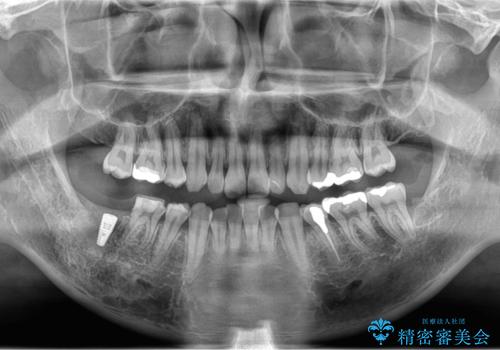

白くて綺麗な被せ物が入りました。

インプラントを入れた後は定期的なメンテナンスが必要になります。